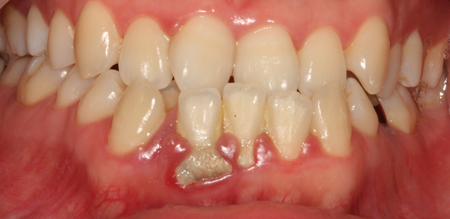

치주치료 전후사진

B

A

치은염 (초기~중기)

치아 주위의 잇몸이 붉게 부어 있으며, 칫솔질 등을 할 때 피가 남.

스케일링 주기의 조절이 필요할 수 있으며, 올바른 칫솔질을 시행하여야 함.

치주염 (중기~말기)

주기적으로 잇몸이 붓고 피가 나며, 욱씬하거나 우리한 통증이 나타남.

치주치료 및 정도에 따라 치주수술(잇몸수술)이 필요함. 향후 관리 정도에 따라 3~6개월 간격으로 내원하여 유지치료를 시행하여야 함.

치주염 (말기)

잇몸이 항상 부어 있으며, 이가

흔들리는 정도가 점점 심해짐.

치주치료가 필요하며, 정도에 따라 치아를 발치하여야 할 수 있음.